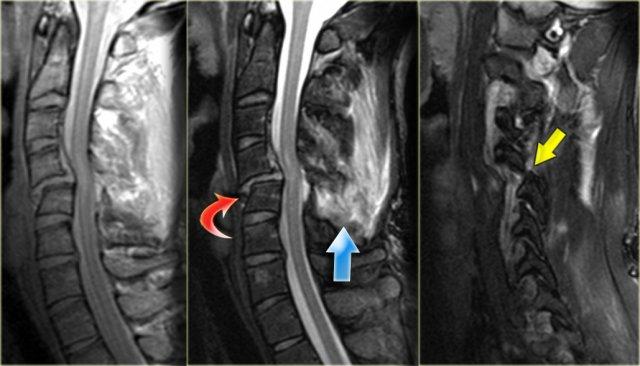

MRI giải thích tình trạng thần kinh của bệnh nhân này.

Các dấu hiệu trên MRI bao gồm:

- Tổn thương mô mềm nặng nề ở các cấu trúc cạnh sống phía sau, đặc biệt tại mức C5-6, nơi dây chằng gian gai và dây chằng vàng bị đứt

- Rách đĩa đệm C5-6 với di lệch ra phía sau C5

- Phù nề tủy sống lan rộng

Tiếp tục với hình ảnh mặt cắt axial.

Hình ảnh axial cho thấy tổn thương tủy sống và ngoài ra còn có sự vắng mặt của khoảng trống dòng chảy (flow void) ở động mạch đốt sống phải.

Điều này gợi ý huyết khối do bóc tách động mạch.

Kết luận, bệnh nhân này không có gãy xương, nhưng có bong gân tăng gấp nặng kèm thoát vị đĩa đệm cấp tính, tổn thương tủy sống không xuất huyết và huyết khối động mạch đốt sống.

Chụp mạch cộng hưởng từ (MRA) xác nhận tắc nghẽn động mạch đốt sống phải.